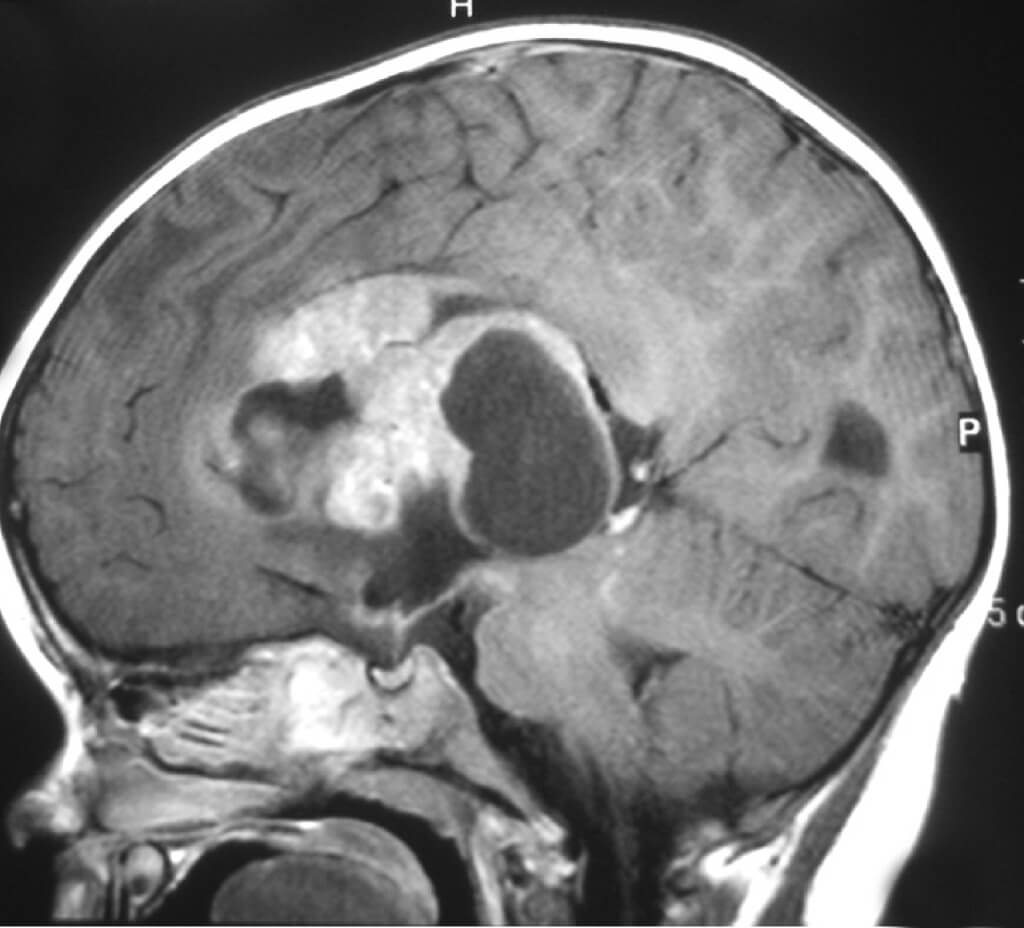

Опухоль без кровотока

Опухоль без кровотока 110 фотографий